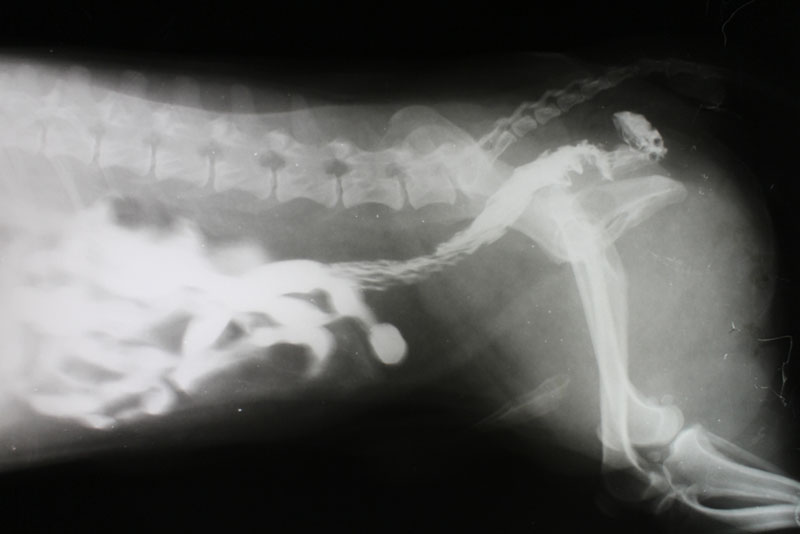

Следующий этап в диагностике – проведение рентгенологического исследования брюшной полости. На снимке будет четко видно количество каловых масс, растяжение кишечника и иногда причины образования калового завала.

при диагностике собаки с запором может потребоваться рентгенологическое исследование